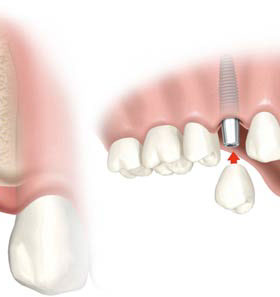

L’assemblaggio tra Impianto e Protesi

Tolta definitivamente la Vite di Guarigione si avvitano i Pilastri, ciascuno per ogni Impianto.

Ogni Pilastro farà da sostegno alla Protesi.